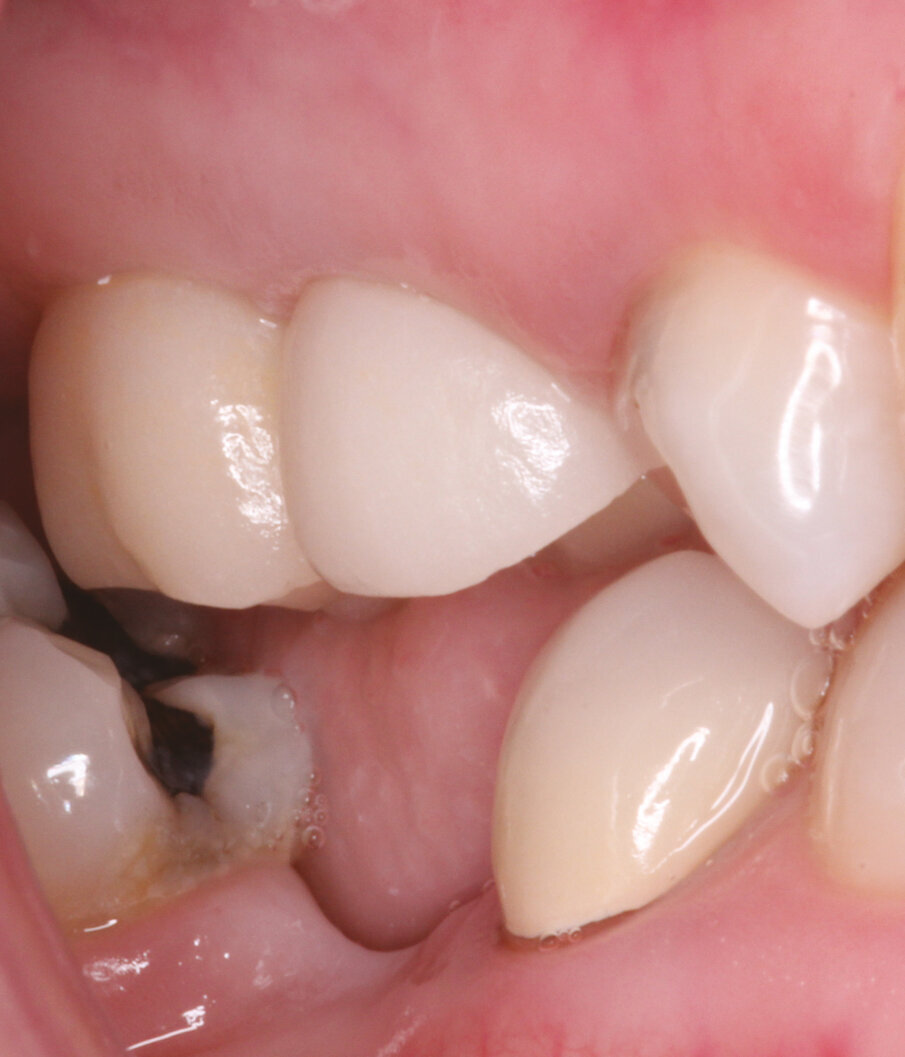

Figs.1-2: Pre Op situation upper right and left sides.

A 43-year-old female presents with missing premolar and molar upper right side (#15,16) and missing premolar upper left (#25). These teeth have been missing for 15+ years. A flapless approach was selected to minimize trauma and to facilitate quick healing. The Axiom Concept was utilized to create an emergence profile that would be difficult to detect from the natural dentition.